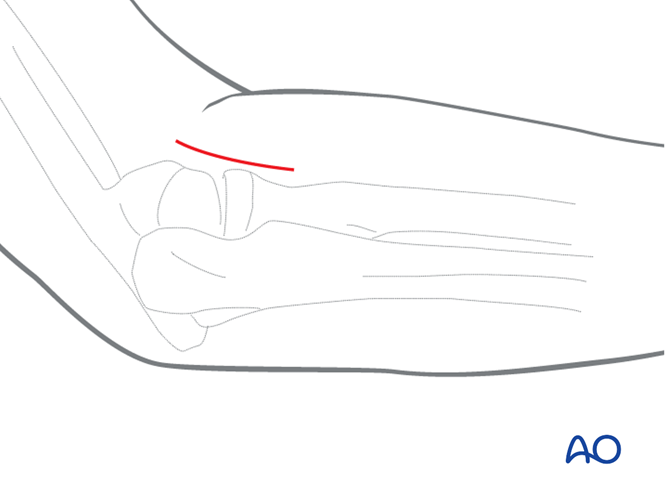

在屈肌与伸肌之间的神经间平面做尺骨中段切口。标记出尺骨近端和远端。